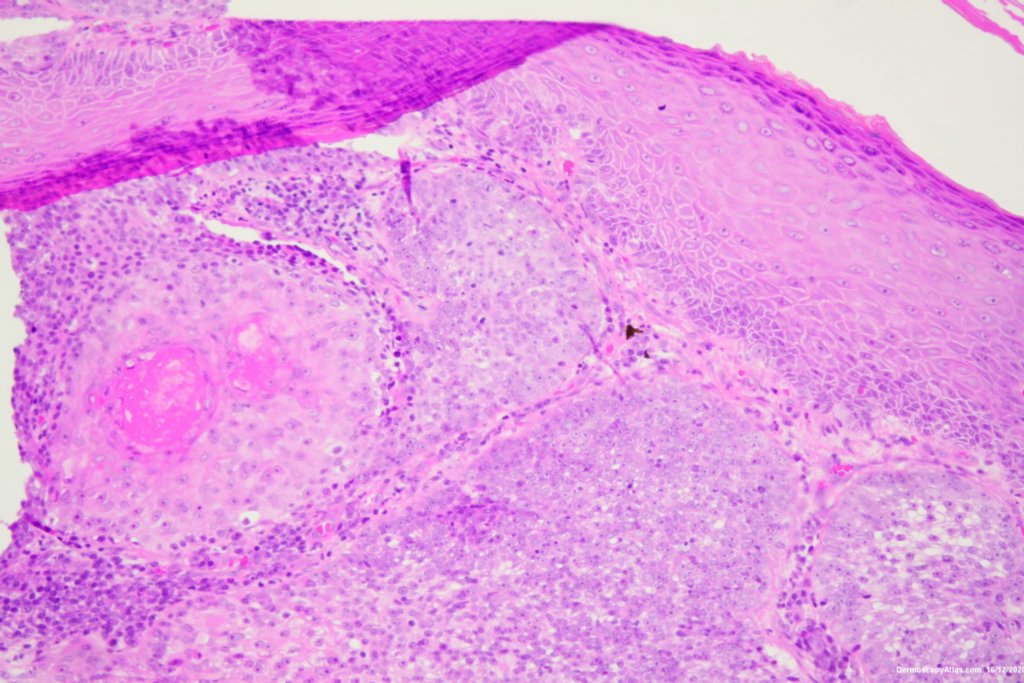

Site: Cheek

Diagnosis: Lentigo Maligna

Description: Pigmented lesion cheek and pink nodule

Elderly male with no past history of melanoma developed these two lesions over a year or so. The lentigo maligna was easy to diagnose on the clinical and dermatoscopy but the nodule was more difficult. Was it an amelanotic melanoma, BCC or SCC were the initial thoughts. Histology showed a well differentiated sebaceous carcinoma. The two lesions were excised in the same specimen with 5 mm margins. Studies failed to show the mutation for the Muir Torre syndrome which can be seen with sebaceous carcinoma.